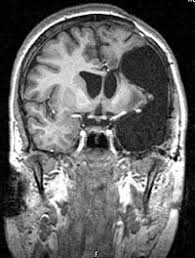

MRI

We saw the pictures of his mri.